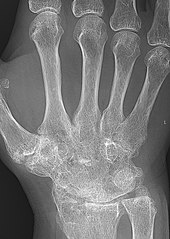

A hand severely affected by rheumatoid arthritis. This degree of swelling and deformation does not typically occur with current treatment.